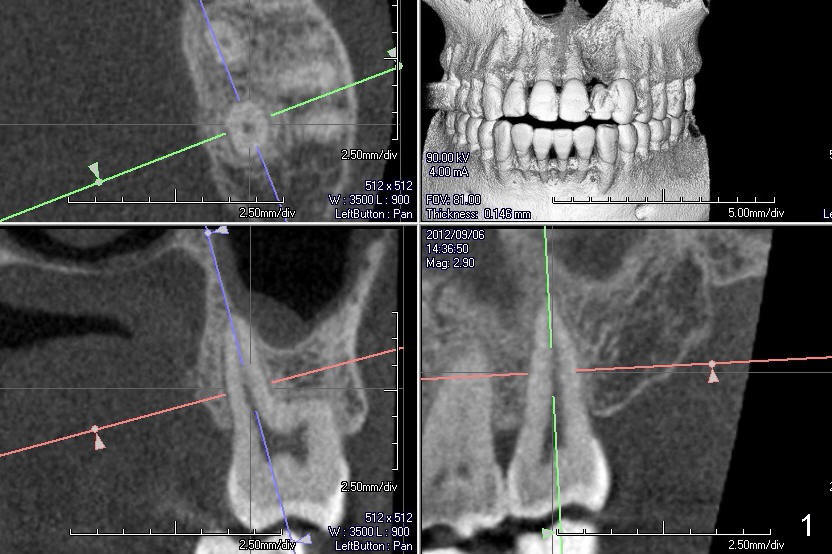

A 60-year-old man requests replacing the teeth #2 and 3, which have root fracture. Both of these two teeth have 3 roots (palatal (P), mesiobuccal (MB) and distobuccal (DB) (X-ray not shown). CT images from a different patient are used instead (Fig.1-3). The upper left image of Fig.1 (i.e., Fig.2) is an axial section, lower left (Fig.3) coronal and lower right sagittal.